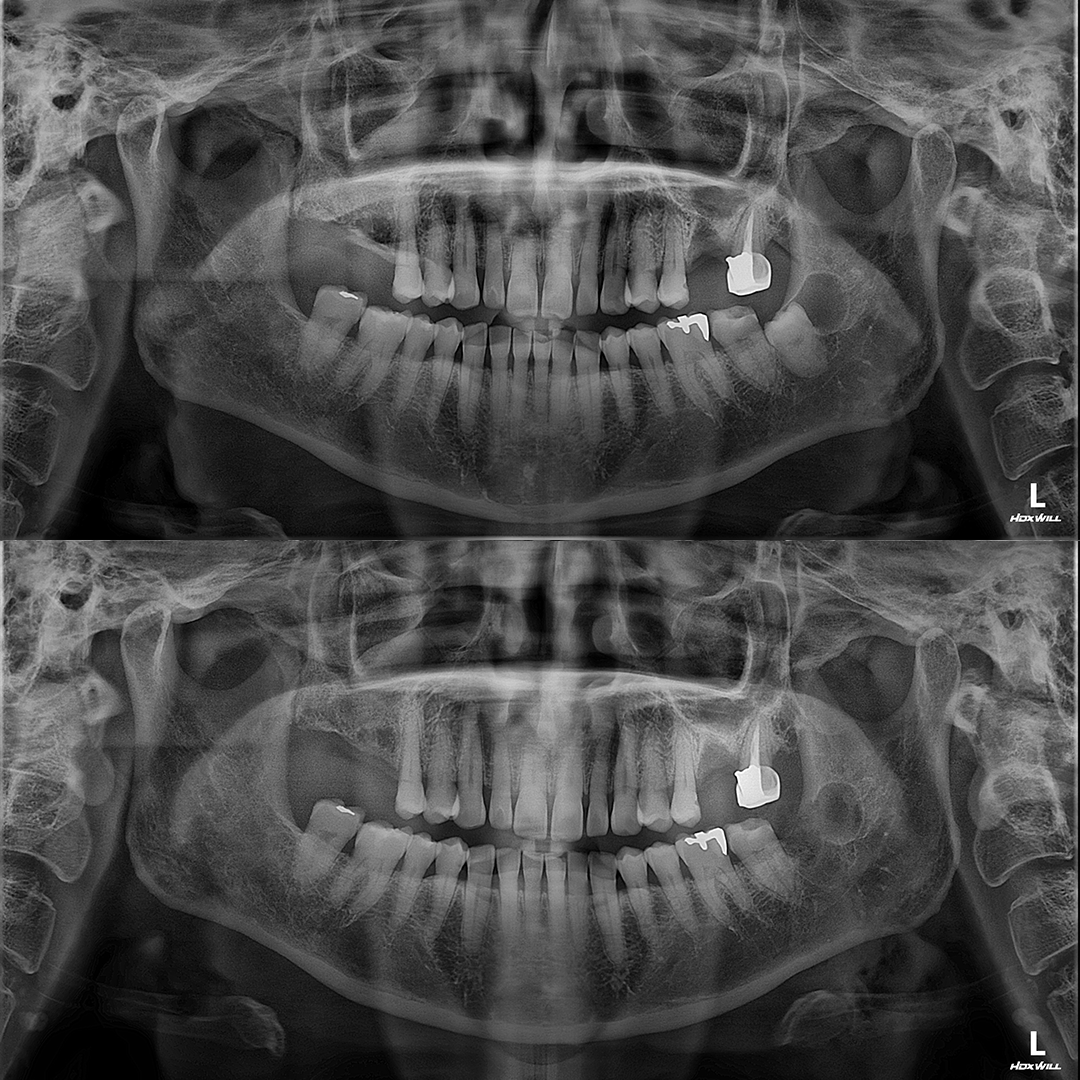

심하게 매복된 어금니 발치를 동반한 임플란트 치료증례

안녕하세요. 도화역치과 365서울앞선치과의원입니다. 오늘은 심하게 매복된 어금니 발치를 동반한 임플..